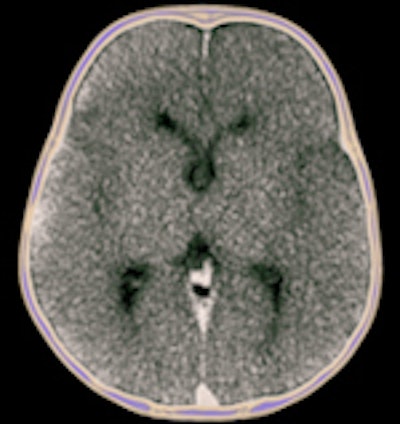

CT and MRI exams were performed during evening and night shifts at times when scanners were not in use for the hospitals' patients. The bodies, contained in sealed body bags, were imaged in the supine position. Two radiologists first independently interpreted the exams, preparing individual reports. They subsequently prepared a consensus report. Additionally, brain scans were reported by a specialist neuroradiologist, and a specialist cardiac radiologist also interpreted findings and prepared a report. All radiologists limited their reports to noting only findings that could pertain to cause of death.

Based on their findings, the radiologists determined that an autopsy could have been avoided for 34% of the cases based on CT exam reports, 42% based on MRI reports, and 48% based on consensus reports. In many cases, imaging proved to be better than autopsy in detecting pneumothorax, intracranial pathologies, and some fractures, the authors wrote.